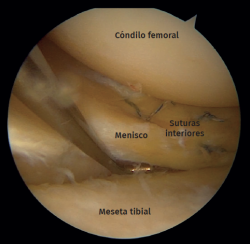

Figure 7. Left knee. View from the anterolateral portal. Peripheral longitudinal meniscus tear suture.

Of the 15 lateral meniscus injuries, there were 9 radial tears treated with partial meniscectomy and 6 peripheral tears that were sutured with a combination of an outside-in and an all-inside technique (Figures 7 and 8).